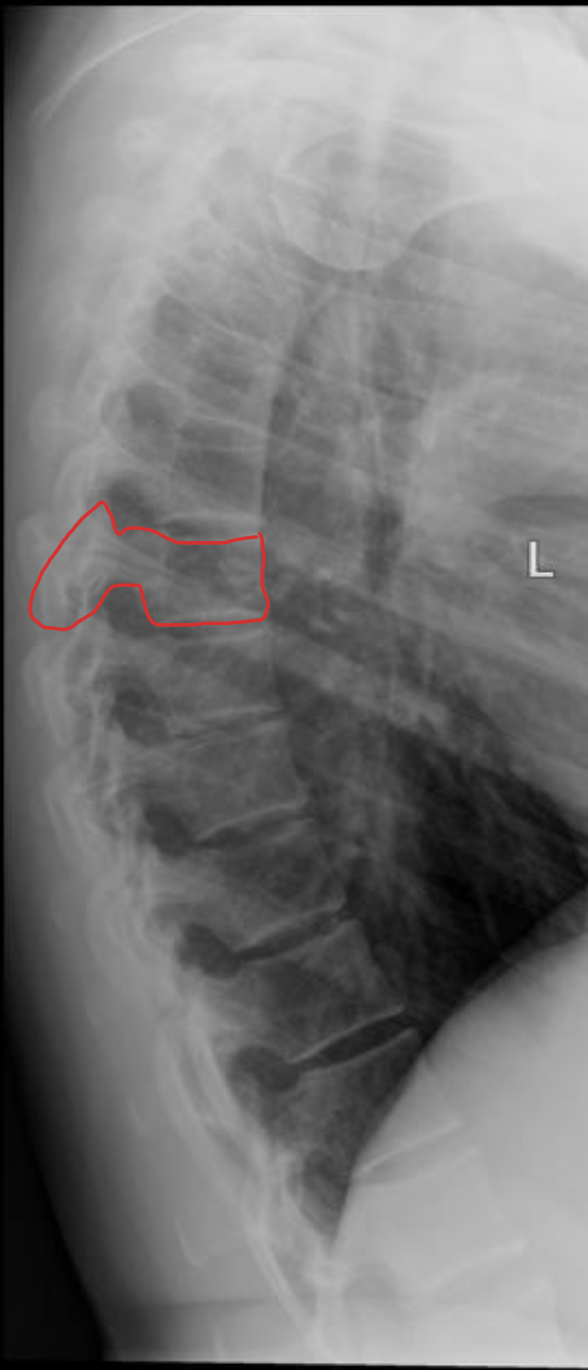

胸椎

THORACIC

T1

T2

T3

T4

T5

T6

T7

T8

T9